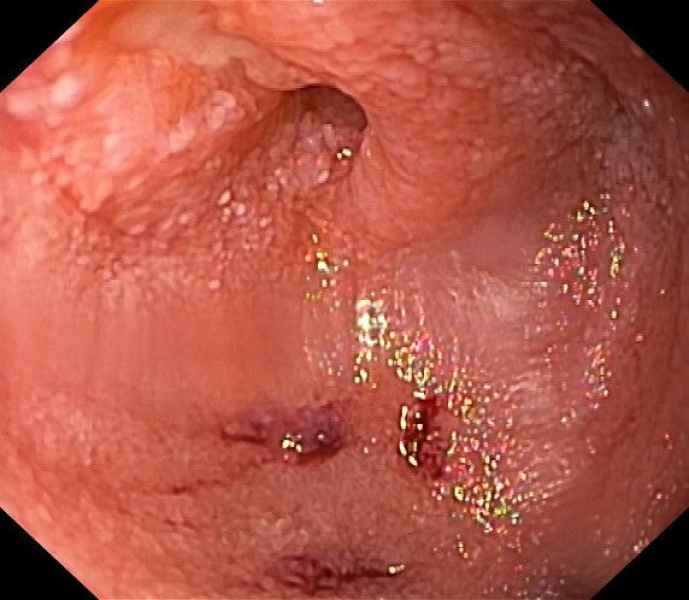

Successful jejunal variceal obliteration with n-butyl-2-cyanoacrylate injection

Fotografia